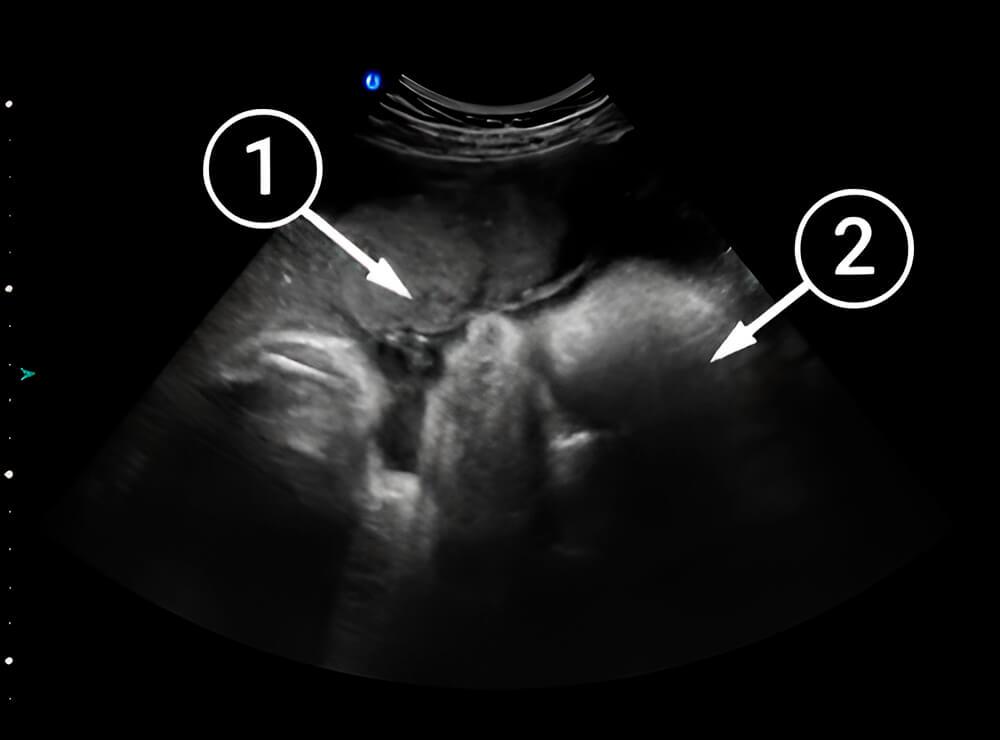

¿Qué se puede ver en la ecografía/ultrasonido?

En la imagen, un bebé yace sobre su lado izquierdo. Se aprecia la vista de cerca de su cabeza: una frente bien definida, sus ojos y nariz, la mandíbula superior e inferior y su barbilla. La placenta es visible encima de ella, todavía alimentando al bebé.